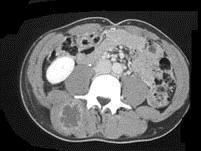

问题 女,28岁,右肾区痛伴高热,请根据所示图像,选择最可能诊断 ( )

选项 A、右侧输尿管下段结石 B、右侧脊柱旁脓肿 C、右侧输尿管上段结石 D、右侧输尿管中段结石 E、右肾结石

答案 B